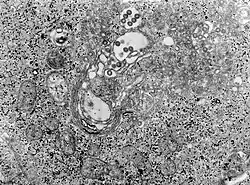

| Tissue infected with the Rift Valley fever virus | |

| Rift Valley fever virus | Rift Valley fever | 2–6 days | Fever, headache, myalgia and liver abnormalities | 4–7 days | Hemorrhagic fever, meningoencephalitis | 1% in humans; in pregnant livestock, 100% fatality rate for fetuses | Culex tritaeniorhynchus and Aedes vexans | Micropteropus pusillus and Hipposideros abae | Eastern, Southern, and Western Africa | Yes |